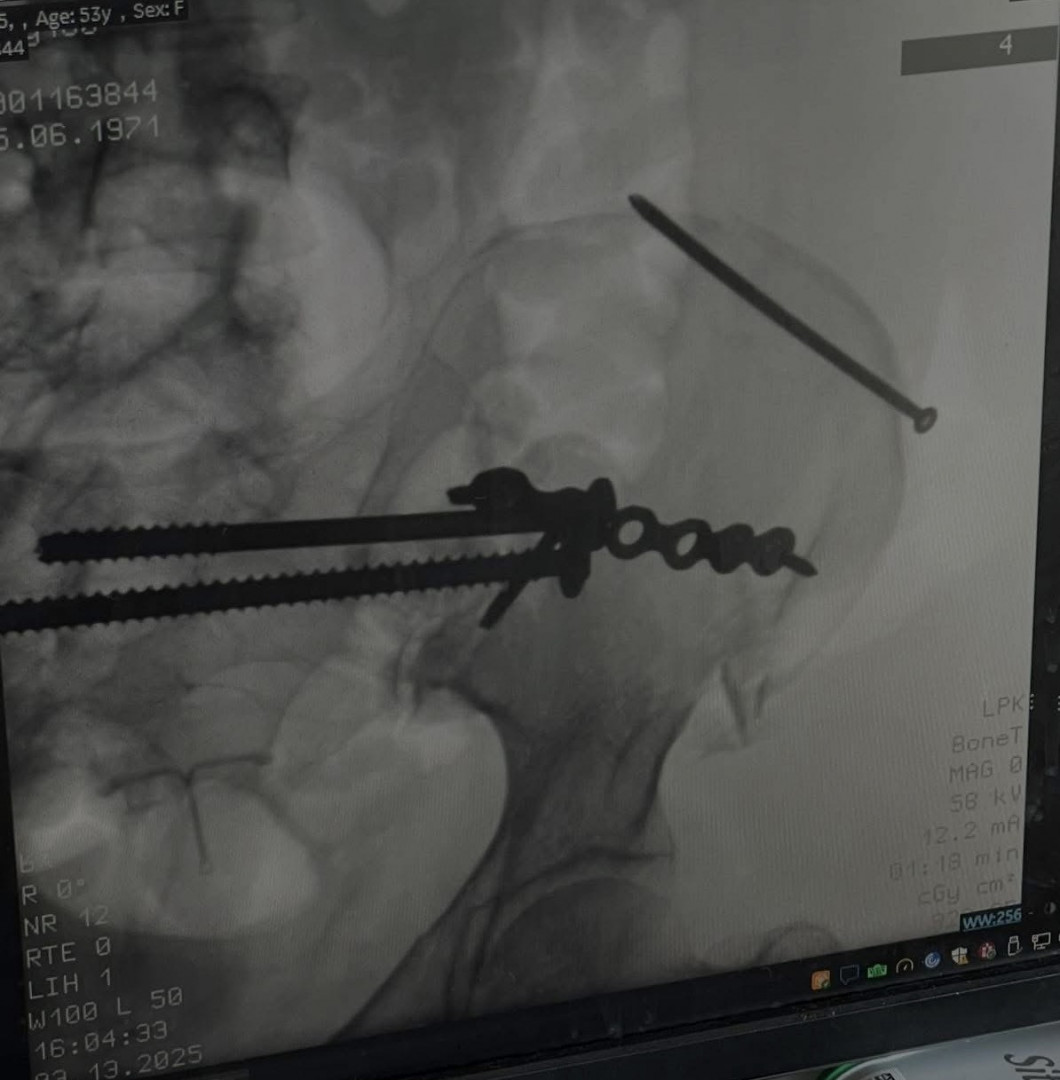

3/12/25 crash left me IMMOBILE with 107 FRACTURES I fought back. Now standing, fueled by nutrition, proof resilience is health

A passion for health and fitness was born in recovery. After a March 2025 car accident left me with 107 fractures and months in a wheelchair, I learned that movement, nutrition, and mindset are life-saving. Every workout and healthy choice is a gift. Fitness isn't about perfection, it's about honoring what my body has overcome. I want to live not just for myself but for my beautiful family, my friends and those who are in my circle cheering me on to get out of that wheelchair and live life.

After my March 12, 2025 accident, I was 53 and IMMOBILE for 3 1/2 months. Severe muscle atrophy, WEIGHT GAIN (25 lbs.), and the TOXIC effects of surgeries and pain meds pushed me to take control of my health. Through nutrition and intentional movement, PT, long walks with my husband or dog, Koko, I began healing my body from the inside out. I'm grateful for the inspiration, motivation, tips, love and support from my friends and coaches at the Looking Good - Feeling Good Facebook Community.